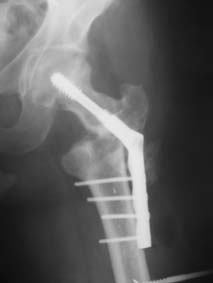

Возможно, пример (в приложении) поможет Вам определиться с выбором

тактики лечения (у нашего пациента, кроме тугого ложного сустава

вертельной области, сложная деформация н/3 бедренной кости; т.к. это

не имеет значения к обсуждаемой теме - оставил "за кадром"). Как Вы

видите, мы в данном случае не вводили чрескостные элементы в зону

установки имплантата. При отказе от наложения опоры на таз (кстати,

она не обязательно может быть громоздкая спицевая; арки со

стержнями-шурупами, введенными в крыло подвздошной вполне достаточно)

"не удивляйтесь", если опора со стержнями-шурупами, введенными в

вертельной области в скором времени дестабилизируется, возникнет

воспаление мягких тканей у чрескостных элементов. Такая опора "имеет

на это право": нагрузка конечности от вершины дистального фрагмента до

кончиков пальцев ляжет на нее. А двух-трех введенных рядом

стержней-шурупов, как их не разноси от фронтальной плоскости, в данном

случае явно недостаточно для адекватной фиксации. + для того, чтобы